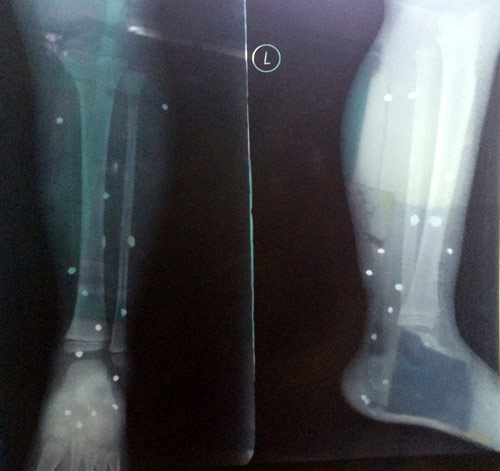

Chân bé Nam bị 15 viên đạn găm vào

Các bác sĩ xác định vùng cẳng chân trái của bé Nam có 15 viên đạn, kích thước khoảng 0,5cm, do bị súng bắn đạn hoa cải gây lên. Chiều cùng ngày, cháu Nam được chuyển lên bệnh viện Nhi trung ương để phẫu thuật, gắp các viên đạn ra.